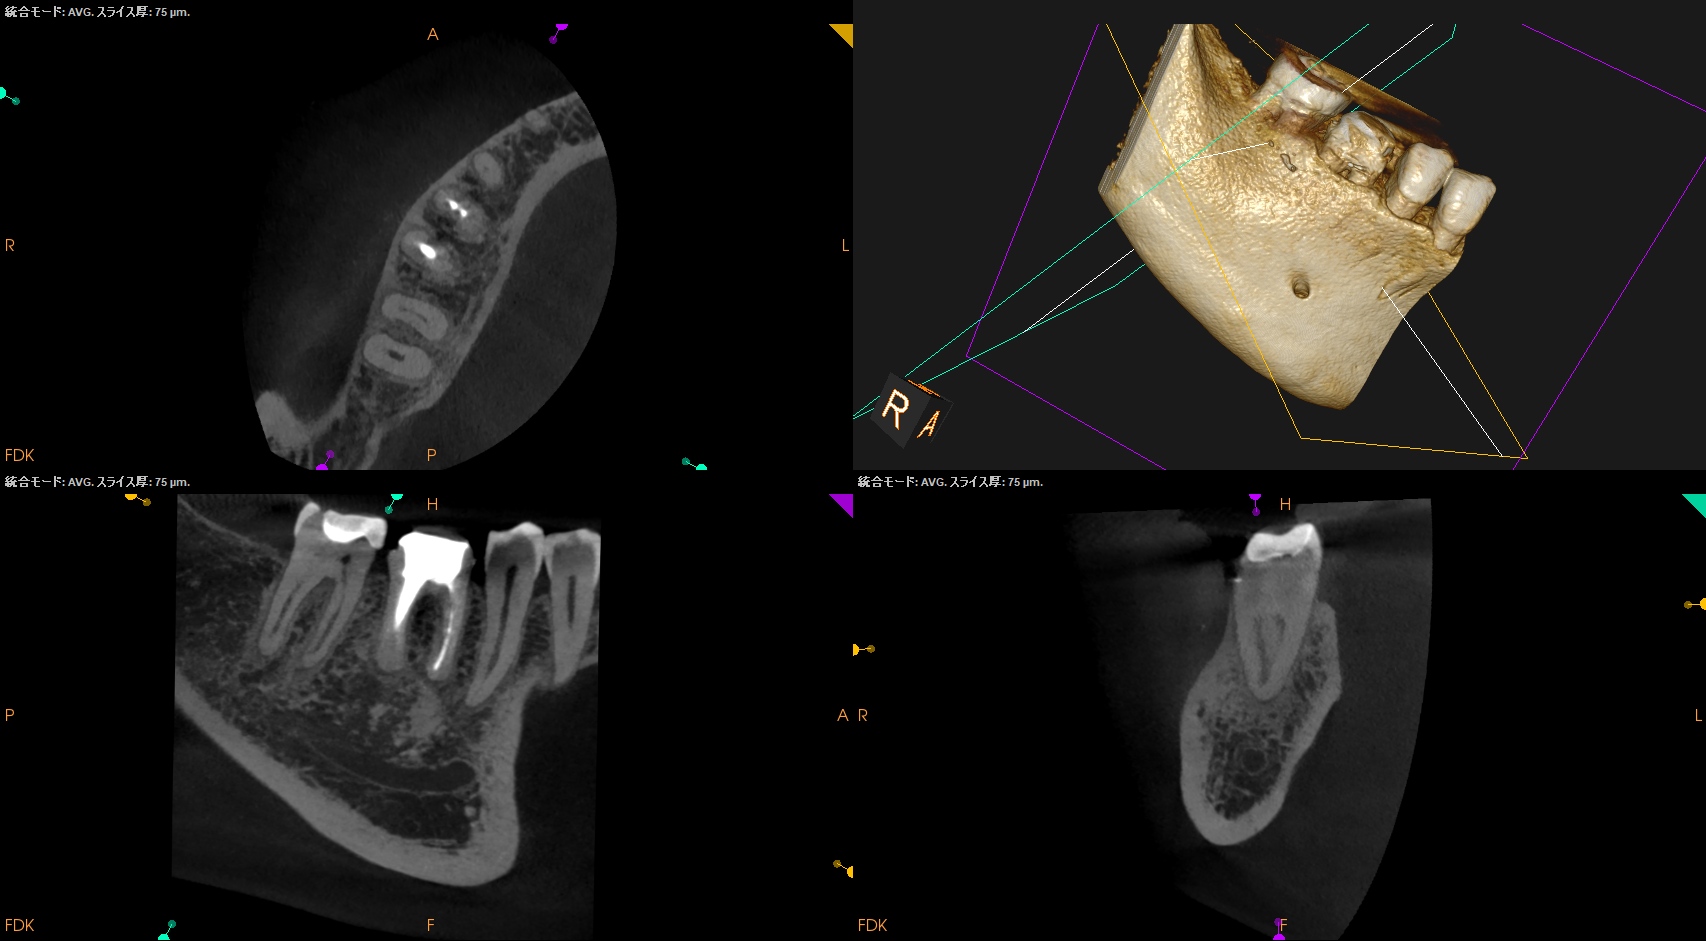

CBCT(2025.8.29)

#30

MB

ML

D